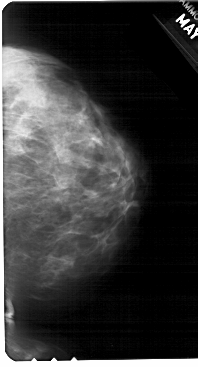

A_1685_1.RIGHT_CC

RIGHT_CC LINES 5491 PIXELS_PER_LINE 2956 BITS_PER_PIXEL 12 RESOLUTION 43.5 NON_OVERLAY